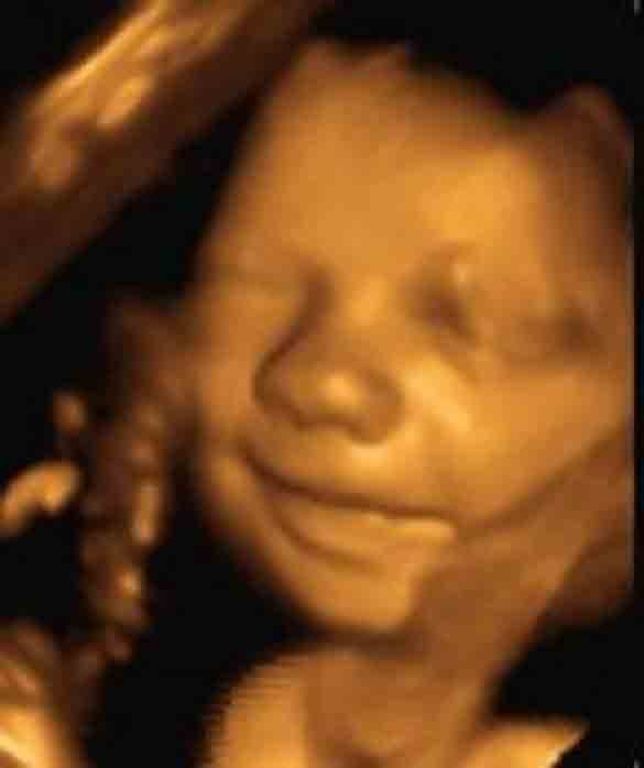

Χάρη στις προηγμένες σύγχρονες τεχνικές , όπως το τρισδιάστατο υπερηχογράφημα, η απεικόνιση του εμβρύου είναι τόσο ρεαλιστική που οι γονείς δεν μπορούν να πιστέψουν ότι αυτό που βλέπουν είναι το μωρό τους.

Υπάρχουν όμως και ορισμένοι υπέρηχοι που ξεχωρίζουν. Είναι διαφορετικοί. Τι εννοούμε; Αποτυπώνουν μια στιγμή που το έμβρυο μπορεί να κινηθεί ή να βρίσκεται σε περίεργη στάση και θέση. Όπως τα μωρά που θα δείτε στη photo gallery που ακολουθεί.

Η αλήθεια είναι ότι ορισμένοι υπέρηχοι είναι αστείοι και άλλοι αρκετά περίεργοι.